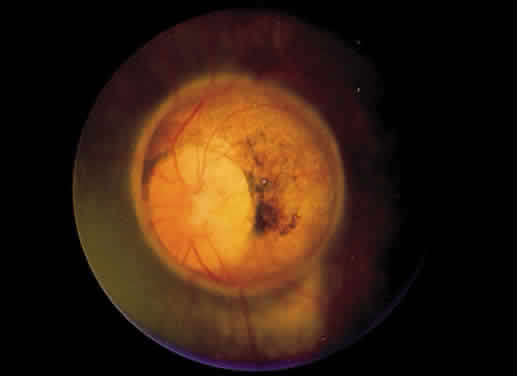

Retinochoroidal colobomas are glistening white or yellow defects with distinct borders that occur inferior or inferonasal to the optic disc (Fig. 12). They may extend up to and involve the optic disc (Fig. 13), or they may be seen as isolated chorioretinal defects. The margins of the coloboma often are pigmented, and the defect is filled with abnormal retinal tissue. Anteriorly, the defect can extend as far as the iris and produce an inferonasal gap (Fig. 14). These anomalies may occur in otherwise normal persons or in association with chromosomal abnormalities or multisystem diseases, such as trisomy 13, the Aicardi syndrome, Goldenhar's syndrome, and the CHARGE association.148,152,153 Occasionally, autosomal dominant or recessive inheritance patterns are found, but often none are evident.152 In families with autosomal dominant inheritance, variable expression of the genetic trait makes genetic counseling difficult.154

Fig. 13. Retinochoroidal coloboma involving the optic disc and inferonasal fundus. The borders of the abnormality are nonpigmented, and the defect appears to be filled with fibroglial tissue.

Embryologically, retinochoroidal colobomas arise from failure of the embryonic fissure to close. Consequently, the inner and outer layers of the optic cup are abnormal in this region. The inner layer (sensory retina) usually is present as a membrane of undifferentiated retina that may have blood vessels going through it (see Figs. 12 and 13). The outer layer (RPE) is absent, and since the choroid is dependent on the RPE for its development, it also is lacking.